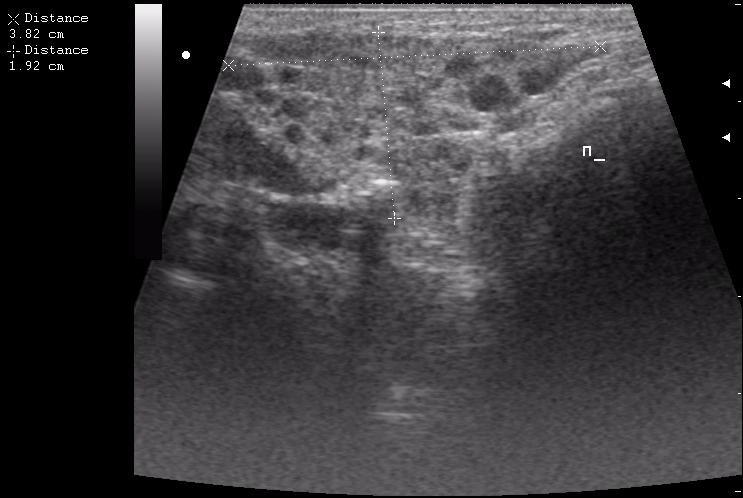

лимфоузел в левой подчелюстной области